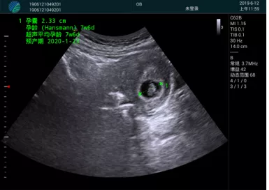

清晰顯示孕囊,通過軟件包計(jì)算孕齡7w+6d

M20實(shí)時(shí)引導(dǎo),術(shù)中清晰顯示孕囊被破壞和抽吸針的過程,清晰顯示吸引針

抽吸結(jié)束后縱切子宮,孕囊已被完全抽吸,未見明顯殘留

橫切子宮,發(fā)現(xiàn)右側(cè)宮腔靠近宮角處有少許脫模樣殘留

M20引導(dǎo)下,抽吸針找到右側(cè)宮角處再次清掃

二次抽吸后再次進(jìn)行超聲檢查,宮腔未見殘留,宮腔線清晰顯示

超聲引導(dǎo)下可視化人流是技術(shù)安全性的保障,一般對(duì)人流術(shù)設(shè)備預(yù)算不高,M20具備婦產(chǎn)科軟件包,且穿透力圖像質(zhì)量好,既滿足人流引導(dǎo)需要,也可用于床旁超聲的需求。